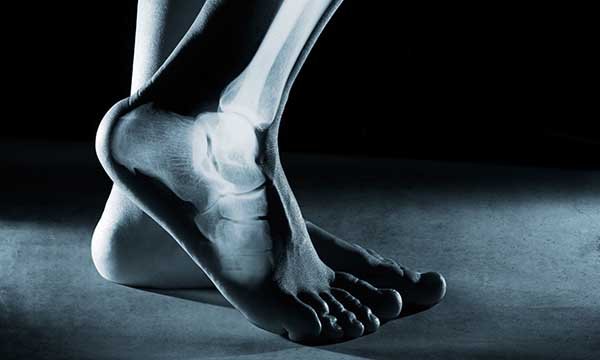

Forearm fractures are most common fractures among children and young people aged up to 19